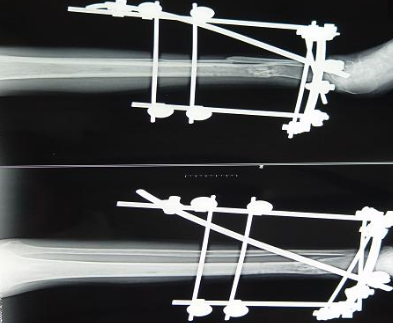

但是从实际应用来看,碳纤维增强peek复合材料零部件所应对的环境中腐蚀因素并非是重要的问题,这些零部件的机械性能相对更为重要。在此情况下,长纤碳纤维增强无疑是比短切碳纤维或粉末碳纤维的增强效果更好。我公司在汲取国外同行先进制造经验的基础上,在长纤碳纤维增强peek复合材料的应用方面取得了很大的进展,不仅通过工艺技术大幅度降低了长纤碳纤维增强peek的成本价格,而且其生产的长纤碳纤维增强peek复合材料骨外科用瞄准器、瞄准架、外固定支架等医疗器械零部件均已达到国际同类产品的质量水准,打破了国内以短切或粉末碳纤维peek复合材料为主的应用格局,为碳纤维增强peek复合材料的应用提供了更多的方向。